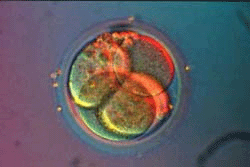

Вторые - начало третьих суток после зачатия. Бластомеров уже восемь. При искусственном оплодотворении (ребенок "из пробирки") в матку женщины подсаживают именно такой зародыш.

Это бластоциста. Похожа на тутовую ягоду?